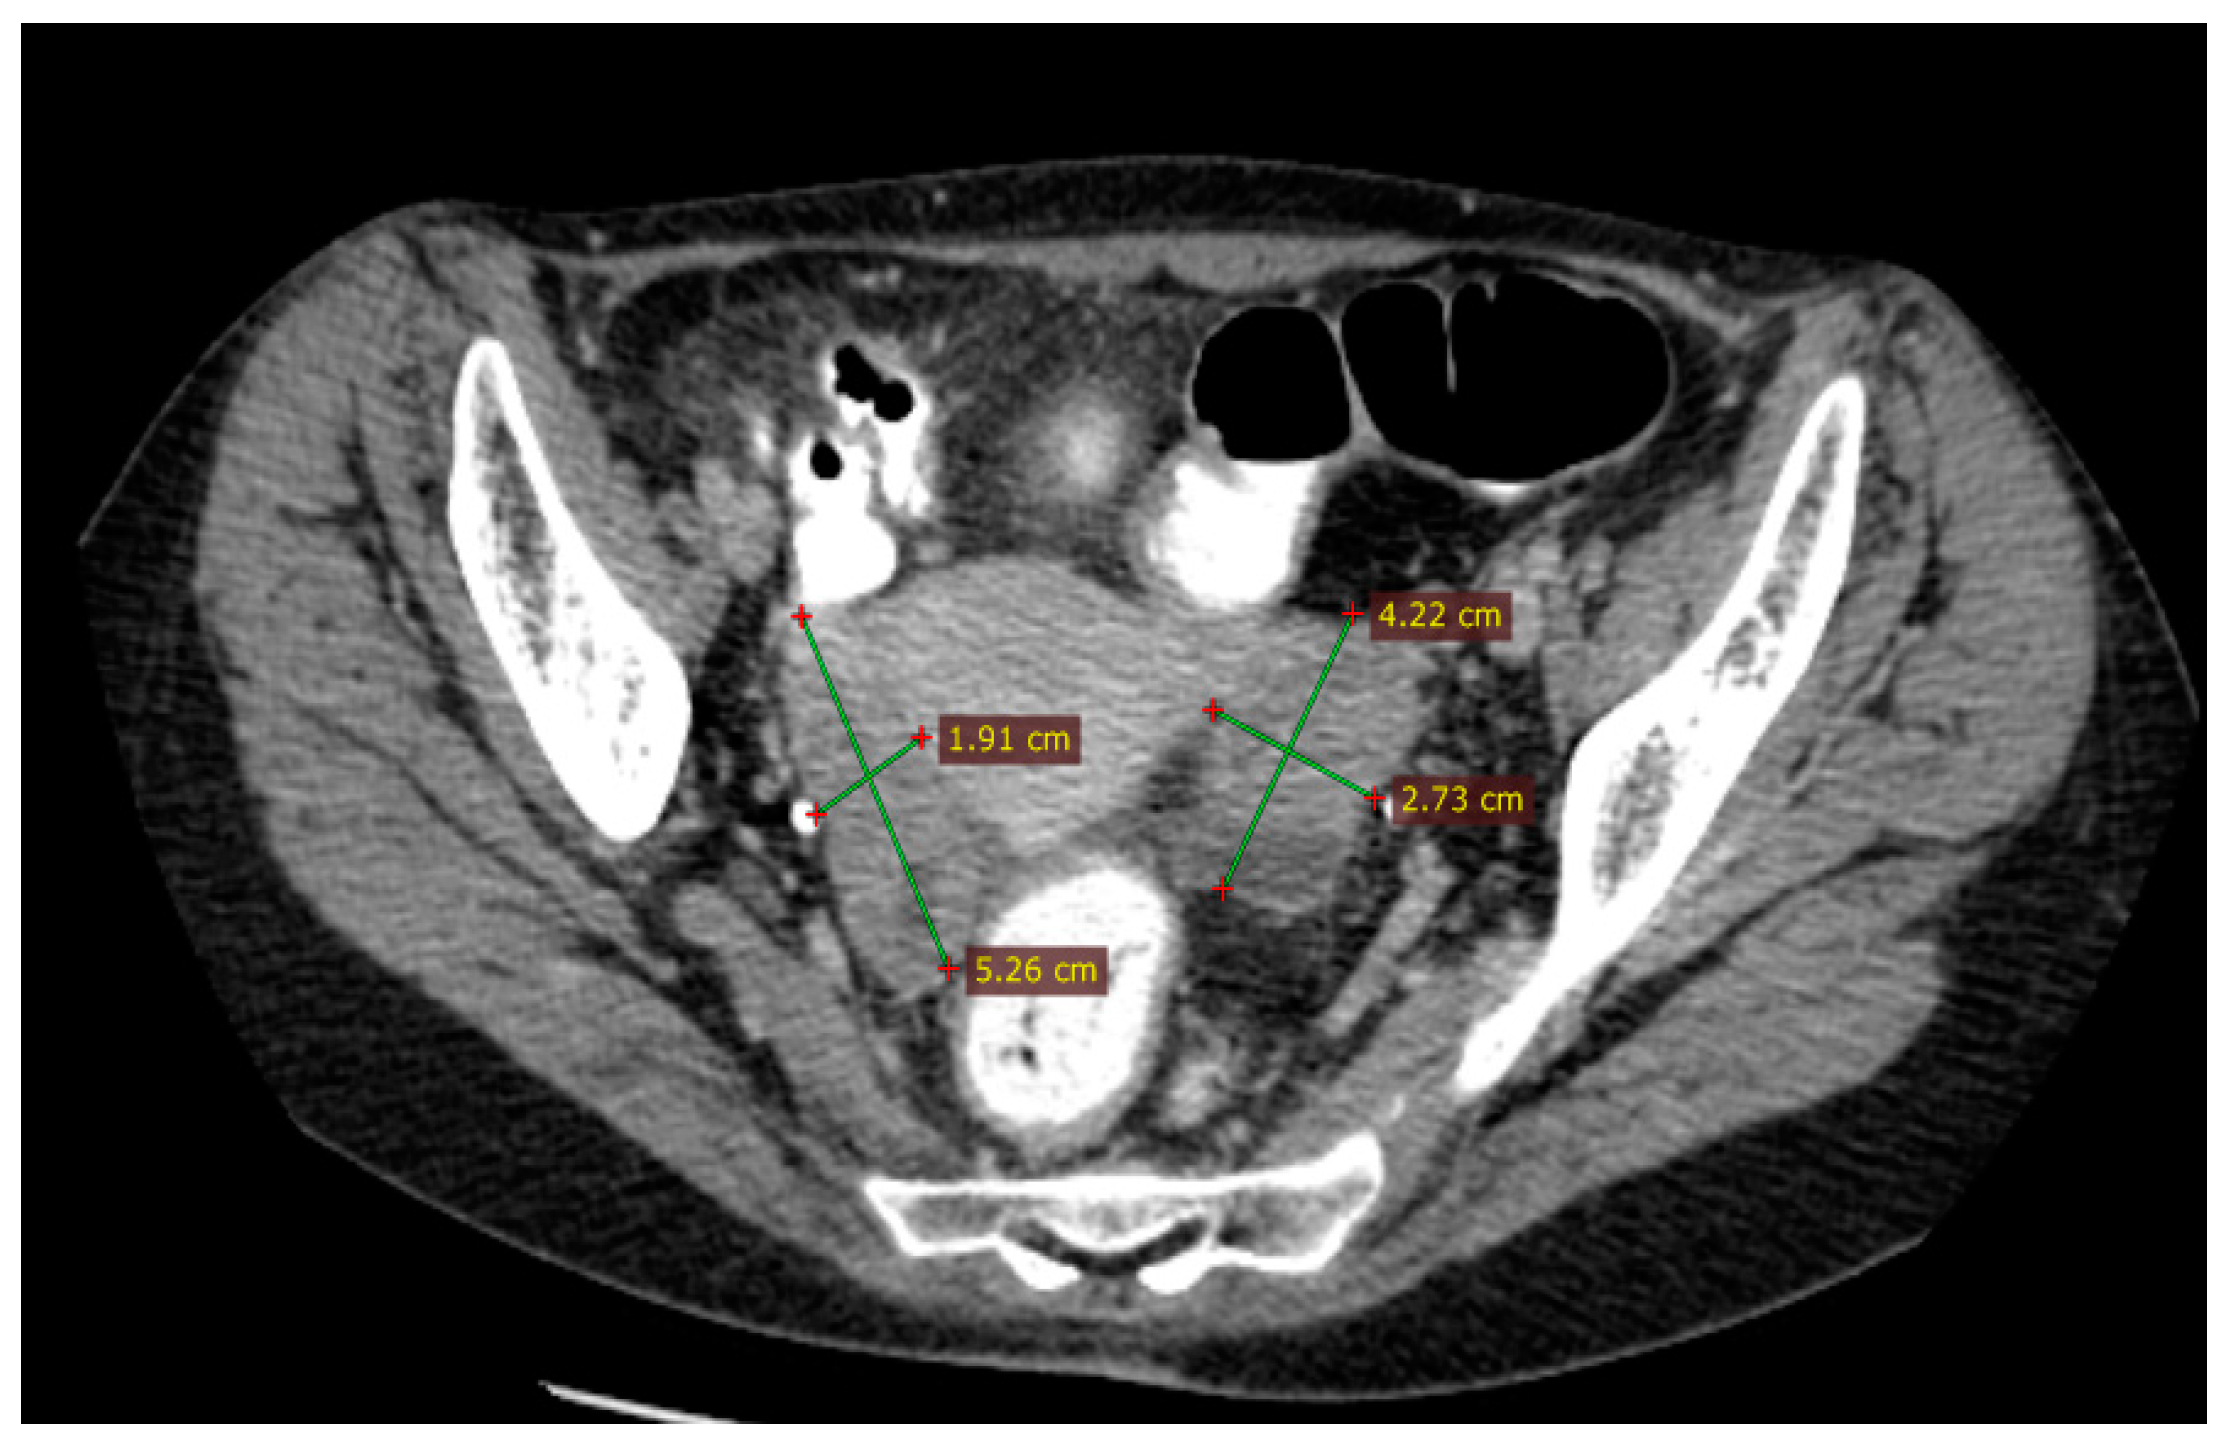

2.2.3. Examinations and Investigations

2.2.5. Treatment and Outcomes

2.2.6. Follow-Up